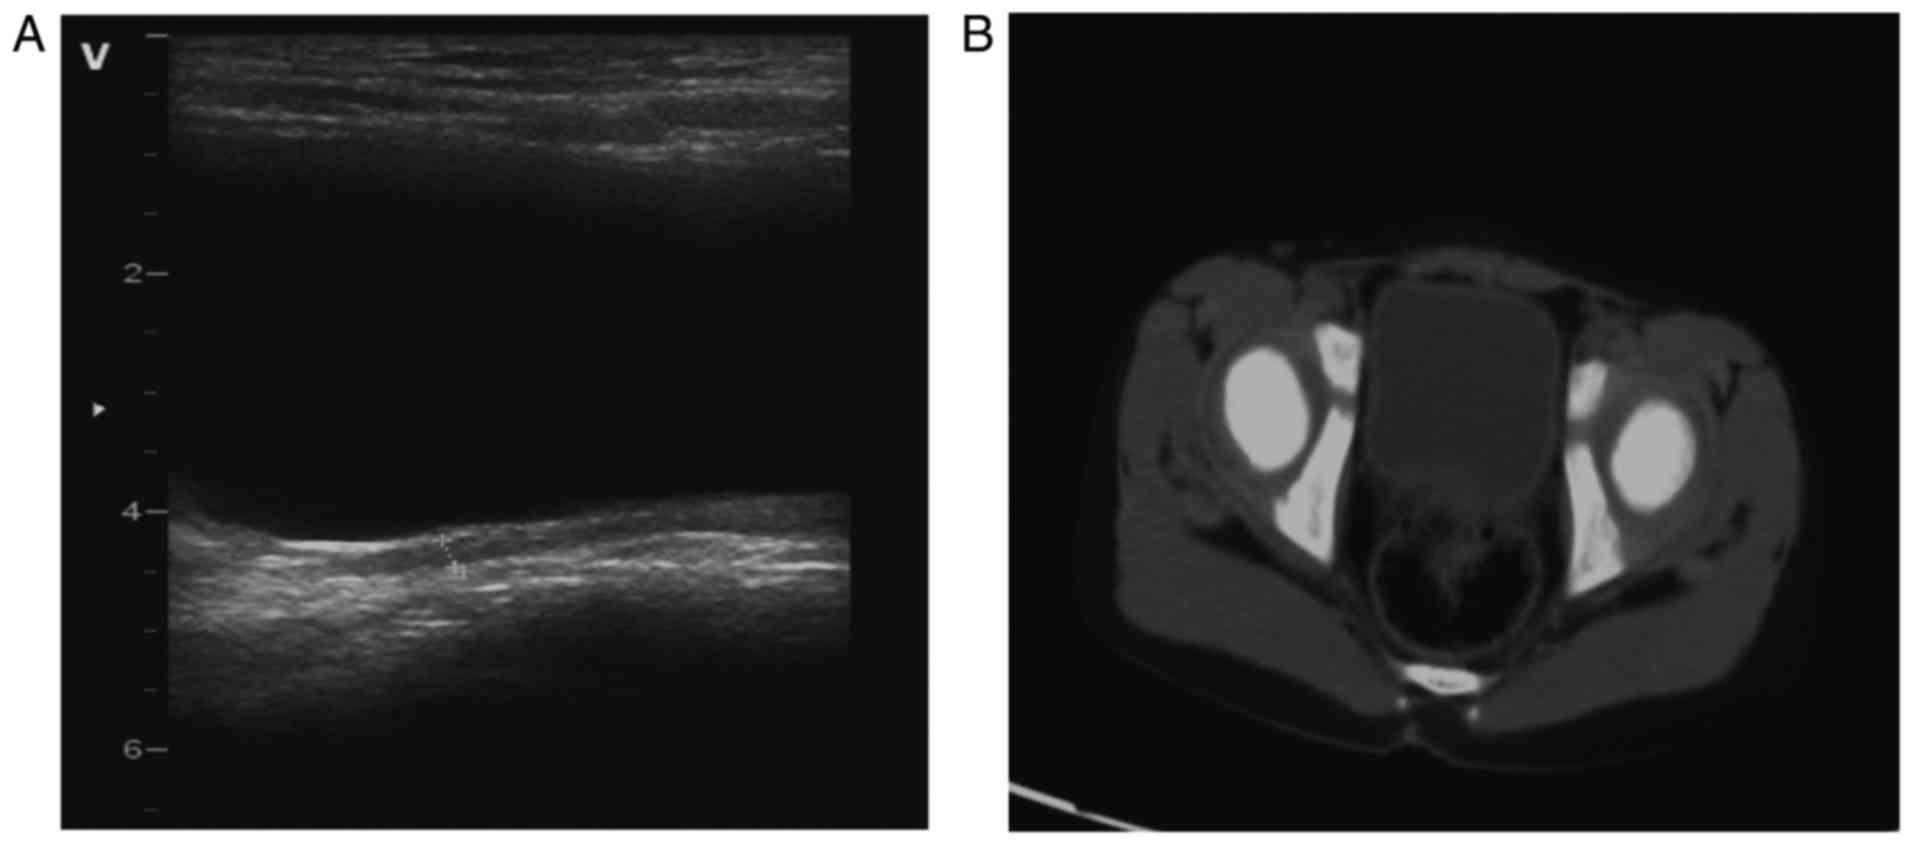

Ultrasound At Clinical Recurrence Showed Thickening Of The Bladder Wall Download Scientific Diagram

Thickening Of The Left Lateral Wall Of The Urinary Bladder Seen On The Download Scientific Diagram